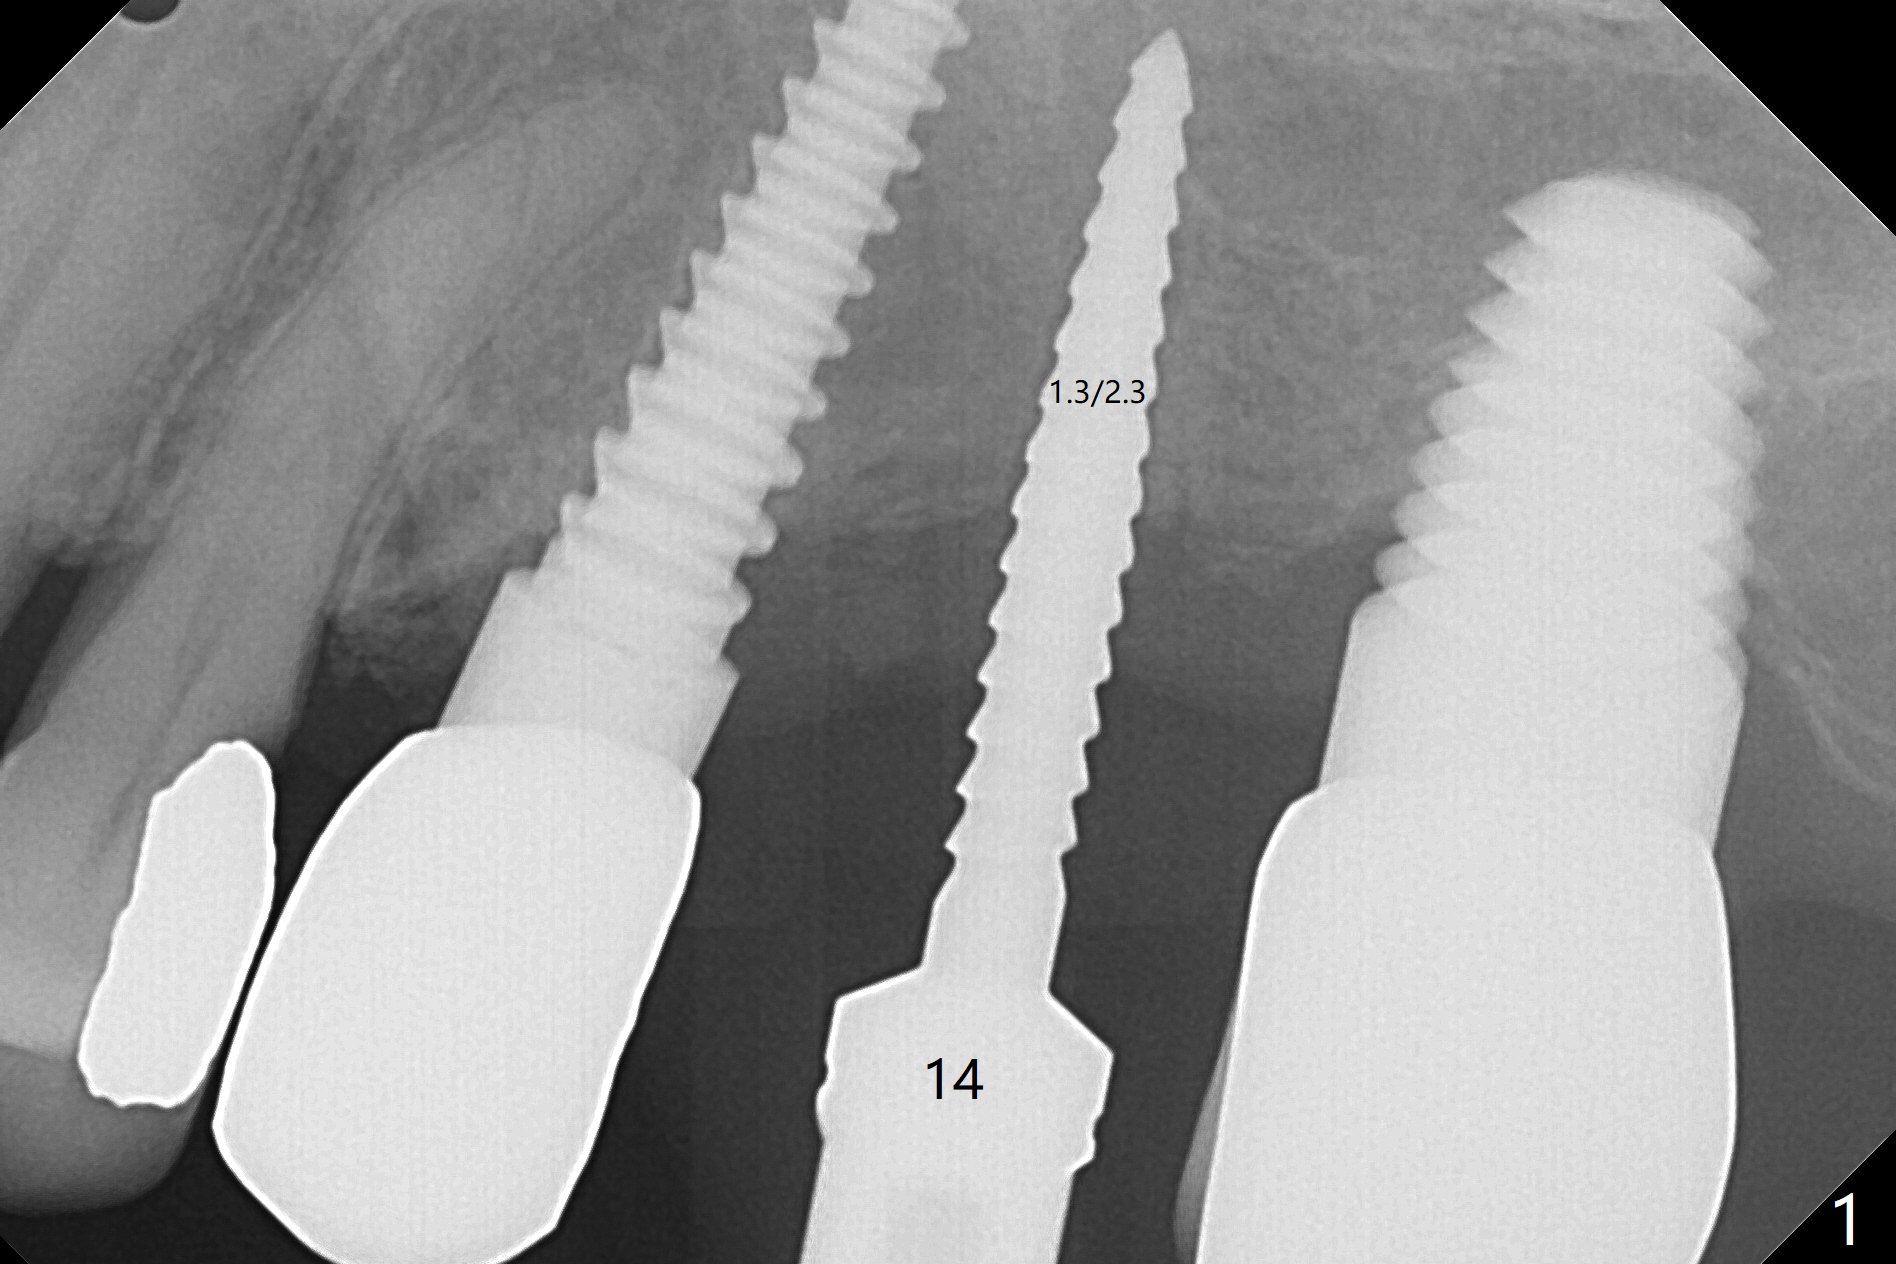

After osteotomy with guide and 2.2 mm drill for ~ 4 mm at #14, a bone expander (1.3/2.3 mm) is used free hand for sinus lift for 12 mm (from the gingival margin, Fig.1; a 10 mm long implant is planned). Following the next expander (1.7/3.1 mm) for the same depth with binding, the sinus membrane is suspected to have perforated. A piece of Osteogen Plug is inserted into the osteotomy as deep as possible with the purpose to repair the sinus membrane (no bone graft being used), followed by placing a 3.5x8.5 (instead of 10) mm implant with insertion torque ~ 25 Ncm (Fig.2,7-9, CT). As compared to preop CT (Fig.4-6), the previously grafted bone is lifted into the sinus by the bone expanders and the implant (Fig.7*). At the same time, the grafted bone has been condensed and pushed buccally (B) (Fig.8,9 *). A 4x6 mm healing abutment is inserted (Fig.3). There is crestal bone loss 6 months postop (Fig.10). Buccal plate atrophy involves the 3 implants in a row (Fig.11). The crown is loose 1 year 8 m post cementation (Fig.12). After proximal reduction, the crown/abutment rotates and sits down substantially (Fig.13). Since the crown is extremely long, it cannot be seated together with the abutment. The latter is seated with X-ray confirmation before proximal reduction of the crown (Fig.14).